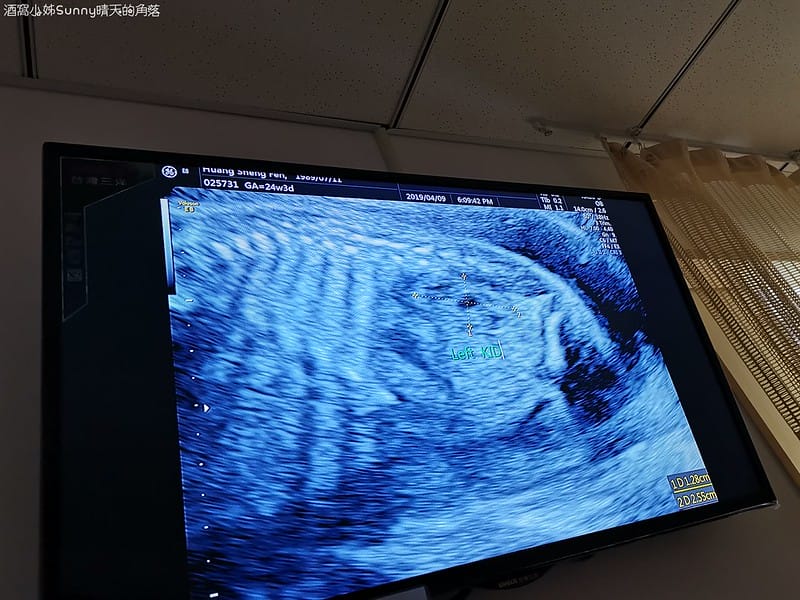

▼這個是寶寶的腎臟❤